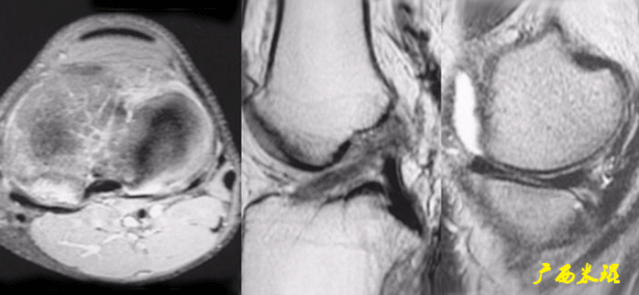

(八)ACL损伤间接征象:

1)ACL撕裂后胫骨前移位出现的一系列改变

2)骨挫伤:

一旦ACL撕裂,胫骨就相对于股骨前移,使股骨外侧髁和胫骨外后方撞击,双方均出现水肿,而且膝关节屈曲的程度决定股骨髁挫伤的部位。

3)沟槽征:

当股骨外髁骨因撞击造成的凹陷深度>2mm时称为沟槽征,代表受到撞击的暴力更大。

4)接吻征:

A.膝关节过伸受伤时,胫骨前部撞击股骨髁前部,形成对称性骨挫伤。

B.如果同时有一外翻力的话,膝关节外侧可出现对称性挫伤,这种对称性骨挫伤称为接吻征。

C.也有人把轴移造成的股骨外侧髁和胫骨外后方水肿称为接吻征。

5)Segond骨折:

胫骨平台前外侧撕脱骨折(胫骨平台腓骨尖上方,关节线下方的撕脱骨折),多因为下肢过度内翻加内旋暴力所致。

骨折本身无特殊治疗,但其强烈提示ACL损伤(75–100%)。

6)胫骨前移:

胫骨后缘垂直线位于股骨髁后缘垂直线前方5mm以上。

由于MRI检查时病人为平卧位,胫骨应该因重力而后沉,因此胫骨前移征往往暗示膝关节处于交锁状态。

7)外侧半月板后角裸露征:

外侧半月板后角后缘垂直线位于胫骨后缘皮质垂直线之后方。